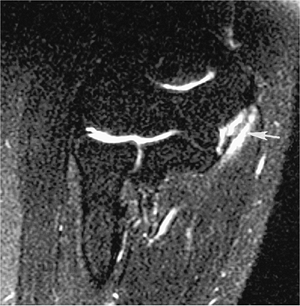

![]() |

FIGURE 8-33 Osteoarthritis. (A) AP radiograph showing bone sclerosis and osteophytes typical of osteoarthritis. (B) Axial T2-weighted MR image showing a joint effusion with osteophytes (open arrows).